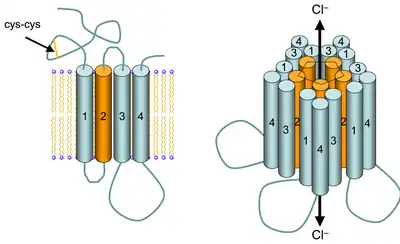

Alcohol also acts as a positive allosteric modulator of GABA receptors, specifically type GABAA.[10] Upon activation, these GABA receptors conduct Cl-, resulting in neuronal hyperpolarization. This hyperpolarization decreases the chance of an action potential occurring and thus, it has an inhibitory effect on neurotransmission in the central nervous system. GABAA receptor subtypes vary in their sensitivities to dosage of alcohol consumed. Furthermore, acute alcohol intake promotes GABAergic neurotransmission via the presynaptic release of GABA, the dephosphorylation of GABAA receptors (increasing GABA sensitivity), and the elevation of endogenous GABAergic neuroactive steroids.[11] Protein kinase C (PKC) has been implicated in differentially modulating the response of the GABAA receptor to alcohol, with effects depending on the PKC isozyme.[12] Alcohol effects have also implicated protein kinase A in affecting GABAA receptor function, such as promoting sensitivity.[13] Enhancement of GABAergic transmission due to alcohol consumption can also be brought about by neuroactive steroids, such as allopregnanolone, which act as GABAA receptor agonists.[11][14] Both chronic alcohol consumption and alcohol dependence are correlated with the altered expression, properties, and functions of the GABAA receptor that may contribute to alcohol tolerance.[11] There is still much yet to be discovered about alcohol's specific and varying effects on both the GABAA receptor and its subtypes.

At higher doses, ethanol also affects NMDA receptors (NMDARs) by inhibiting the ion current induced by NMDA, a glutamate receptor agonist.[15] This inhibition of synaptic excitation by alcohol has been shown to be dose-dependent (up to a certain point, after which it did not differ by much).[16] Alcohol appears to produce this inhibition by using a site of the NMDAR that is accessible from the extracellular environment.[17] Therefore, this inhibition of an ion current usually produced by NMDAR activation leads to decreased LTP in hippocampal areas.[18] Alcohol negatively affects LTP to a greater degree in immature versus mature animals.[19] In adolescents, alcohol decreases the expression of both the NMDAR NR2A subunit in the hippocampus and the NR1 subunit in the prefrontal cortex.[20] Studies have also found that a decrease in phosphorylation of 2B subunit in the prefrontal cortex, the hippocampus, the nucleus accumbens, and the striatum.[21] NMDARS may be affected by PKA regulation due to the actions of alcohol.[22] Alcohol's effects on GABAA neurotransmission may indirectly inhibit the activity of the NMDAR, and they may contribute to its blockade of LTP induction; however, alcohol's direct effects on NMDAR alone are sufficient for the inhibition of LTP.[23] The varying dose-dependent response to alcohol relies on the combined interactions and responses of the GABAA receptors, NMDARs, and metabotropic glutamate receptors subtype 5 (mGluR5).[24][25][26] These changes prevent excitatory synaptic transmissions from occurring, affecting synaptic plasticity and, in turn, memory and learning. However, there is still much yet to be elucidated concerning specific molecular mechanisms of how alcohol affects memory formation.